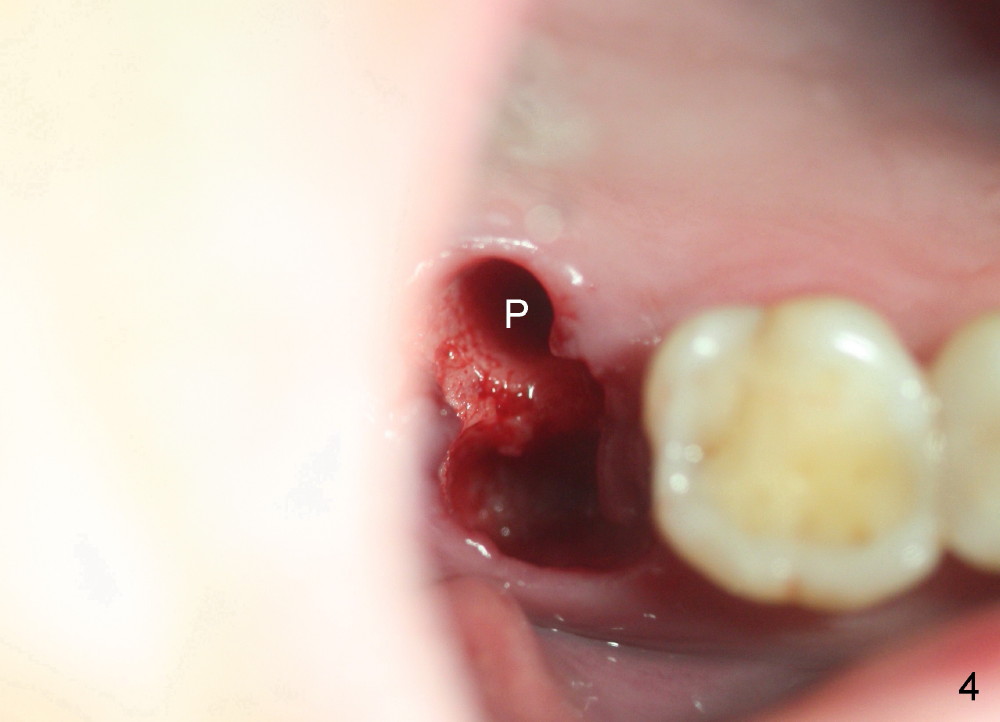

By contrast the palatal socket is deep and relatively small (Fig.4 P), easy to insert taps without drills. When a 7x11 mm tap is placed (Fig.5 T), the coronal end is more or less near the lingual cusps (functional cusps). Although the 7x14 mm tap (Fig.6 T) and a 7x11 mm implant (Fig.7 I) look poking into the maxillary sinus, they are in fact within the palatal socket (Fig.10c). Allograft and Osteogen are placed in the buccal socket (Fig.7 *), followed by collagen dressing (Fig.8 *). A 5x5 mm abutment is placed (Fig.8 A). An immediate provisional (Fig.9 P) is cemented to keep the graft and collagen dressing in place.